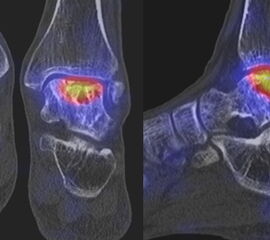

Abbildung 2.3.

Klärung bei Schmerzen im rechten OSG bei OCL an der medialen Talusschulter. Z. n. OSG-Distorsion vor 2 Jahren und Z. n. OSG-Fraktur / Syndesomosenruptur. Ausgedehnte OCL, hier jedoch kein erhöhter Knochenmetabolismus; lediglich Nachweis einer Stressreaktion im Bereich der Synchondrose eines Os trigonum als Schmerzursache.

Zum Lesen der Bildbeschreibung und zur Vollansicht bitte das Bild anklicken. Bild: H. C. Rischke